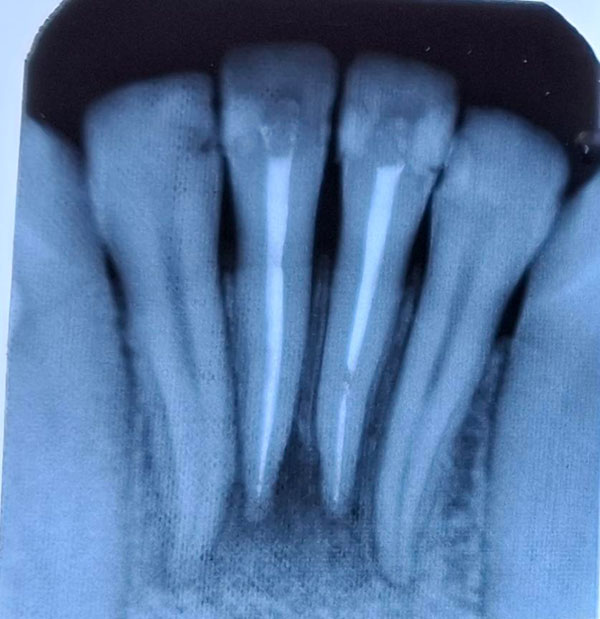

На интраоральной радиограмме корневые каналы зубов 3.1, 4.1 запломбированы плотно гомогенно на всем протяжении до анатомической верхушки. Пространство периодонтальной связки равномерной ширины на всем протяжении. Структура костных балочек восстановлена.